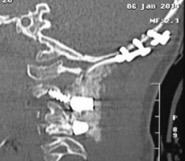

- Figura 2. Tomografia Axial. Inestabilidad Atlanto - Axial

- Figura 4. Tomografía reconstrucción 2D. Muesta inestabilidad C1-C2. Hipoplasia de Odontoides